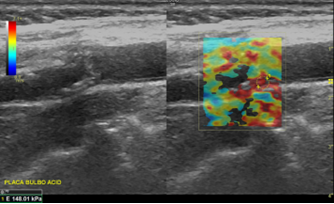

Análisis conjunto de control cardiovascular y elastografía por ondas de corte para determinar la vulnerabilidad de la placa carotíde

La elastografía por onda de corte (SWE) es una modalidad ecográfica avanzada que utiliza pulsos de ultrasonido de alta intensidad para generar ondas de corte dentro de los tejidos. La velocidad de propagación de estas ondas depende de la rigidez: a mayor rigidez, mayor velocidad. Con este principio físico, el sistema calcula el módulo de Young, expresado en kilopascales (kPa), ofreciendo una medida cuantitativa y objetiva de elasticidad.

En el ámbito vascular, esto supone una diferencia fundamental respecto al ecodoppler convencional, que describe el grado de estenosis, la morfología de la placa y las características hemodinámicas del flujo. La SWE no mide el flujo sanguíneo, sino la propiedad biomecánica de la pared y de la placa, lo que permite identificar placas más blandas y potencialmente vulnerables, incluso en ausencia de estenosis críticas.

La estenosis carotídea (CAS) es una causa importante de accidente cerebrovascular (ACV). En pacientes asintomáticos, la decisión de indicar endarterectomía sigue siendo desafiante, ya que el grado de estenosis por sí solo no refleja adecuadamente el riesgo real. La vulnerabilidad de la placa —asociada a componentes blandos y mayor propensión a ruptura— se vincula con mayor riesgo de eventos, pero su evaluación no invasiva sigue siendo un reto. En este contexto, estudios recientes han explorado la utilidad de la SWE, en combinación con otros parámetros fisiológicos como el barorreflejo, para mejorar la caracterización de la vulnerabilidad.